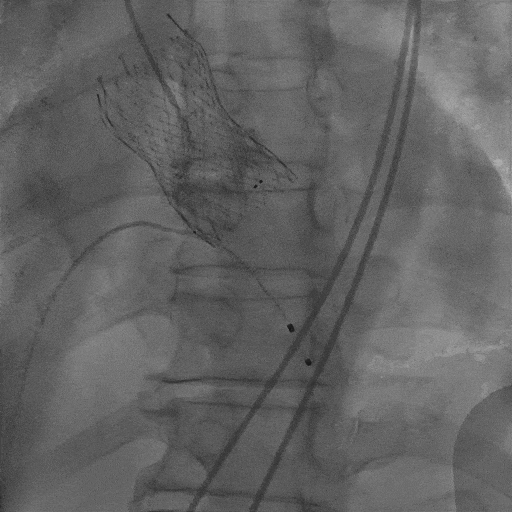

主动脉根部造影

冠脉造影

猪尾跨瓣

左冠保护下THV过弓及跨瓣